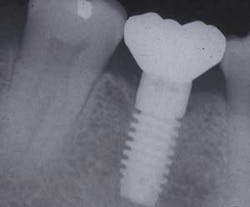

Maintaining natural teeth in health, function, and esthetics is a primary goal of dentistry. In the past, the maintenance of a natural tooth was paramount, because tooth replacement techniques were costly and not as predictable as repairing the natural tooth. What is new in today's environment is that some dental procedures (as the treatment of severe periodontal disease, furcation treatment, or functional crown lengthening) may have a lower success rate or poorer cosmetic result compared to an implant to replace the tooth. Therefore, on occasion, the significantly compromised natural tooth may be extracted and replaced with an implant (right).

Furcation treatment of molars may include root amputation. The lowest success rate for root resection is found in mandibular distal root resections. Even when successful, to extract the distal root requires endodontics on the mesial root, core and crown of the mesial root, and the replacement of the distal root with an implant or fixed partial denture. An extraction of the entire molar and implant insertion has a higher success rate and often lower cost (see photos at right).